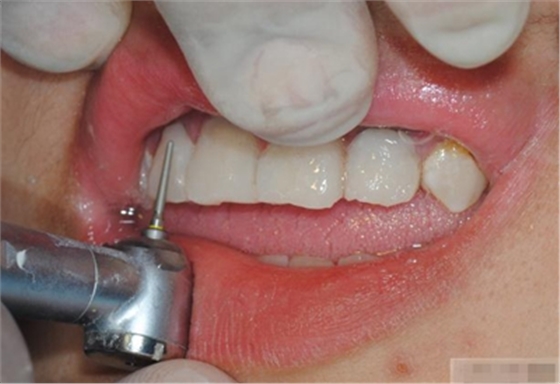

選擇合適的完成鉆制備根管,

通常深入到根管的1/2至2/3處

何種情況應(yīng)該使用纖維樁呢?

是否使用根管纖維樁取決于剩余牙體組織的強(qiáng)度,這主要決定于剩余邊緣嵴的數(shù)量。

a 兩側(cè)邊緣嵴均完整,無(wú)需使用根管纖維樁。

b 一側(cè)邊緣嵴缺如:評(píng)估牙體缺損情況。抗力型有疑慮則加用根管纖維樁。

c 兩側(cè)邊緣嵴均缺如,必須使用根管纖維樁。

在使用根管纖維樁時(shí)根管預(yù)備的深度應(yīng)該是多少呢?

在回答這個(gè)問(wèn)題前,首先應(yīng)該了解根管內(nèi)的粘接狀況。最佳的粘接效果發(fā)生于根管的冠1/3和中1/3。由于根1/3的牙本質(zhì)小管往往不能充分敞開(kāi),此區(qū)域幾乎沒(méi)有粘接作用發(fā)生,所以,根管纖維樁放置的深度無(wú)需超過(guò)根中1/3。同樣重要的是,根管預(yù)備時(shí)鉆的速度不要過(guò)快,防止飛濺的牙膠粘在根管內(nèi)壁上。所以,根管壁的清理也很重要,以確保牙本質(zhì)小管充分開(kāi)放。Dr.Vanini使用噴砂和酸蝕來(lái)充分清理根管壁和窩洞。研究顯示,粘接劑的作用也很重要,粘接根管纖維樁要求使用滲透力強(qiáng)粘結(jié)作用好的粘接劑。

【纖維樁制作】

修整纖維樁長(zhǎng)度

取出纖維樁,按所需長(zhǎng)度裁截纖維樁 在有水條件下 用切割砂片或車針截取纖維樁,切勿使用鉗子,剪刀或鑷子以免破壞樁的結(jié)構(gòu)